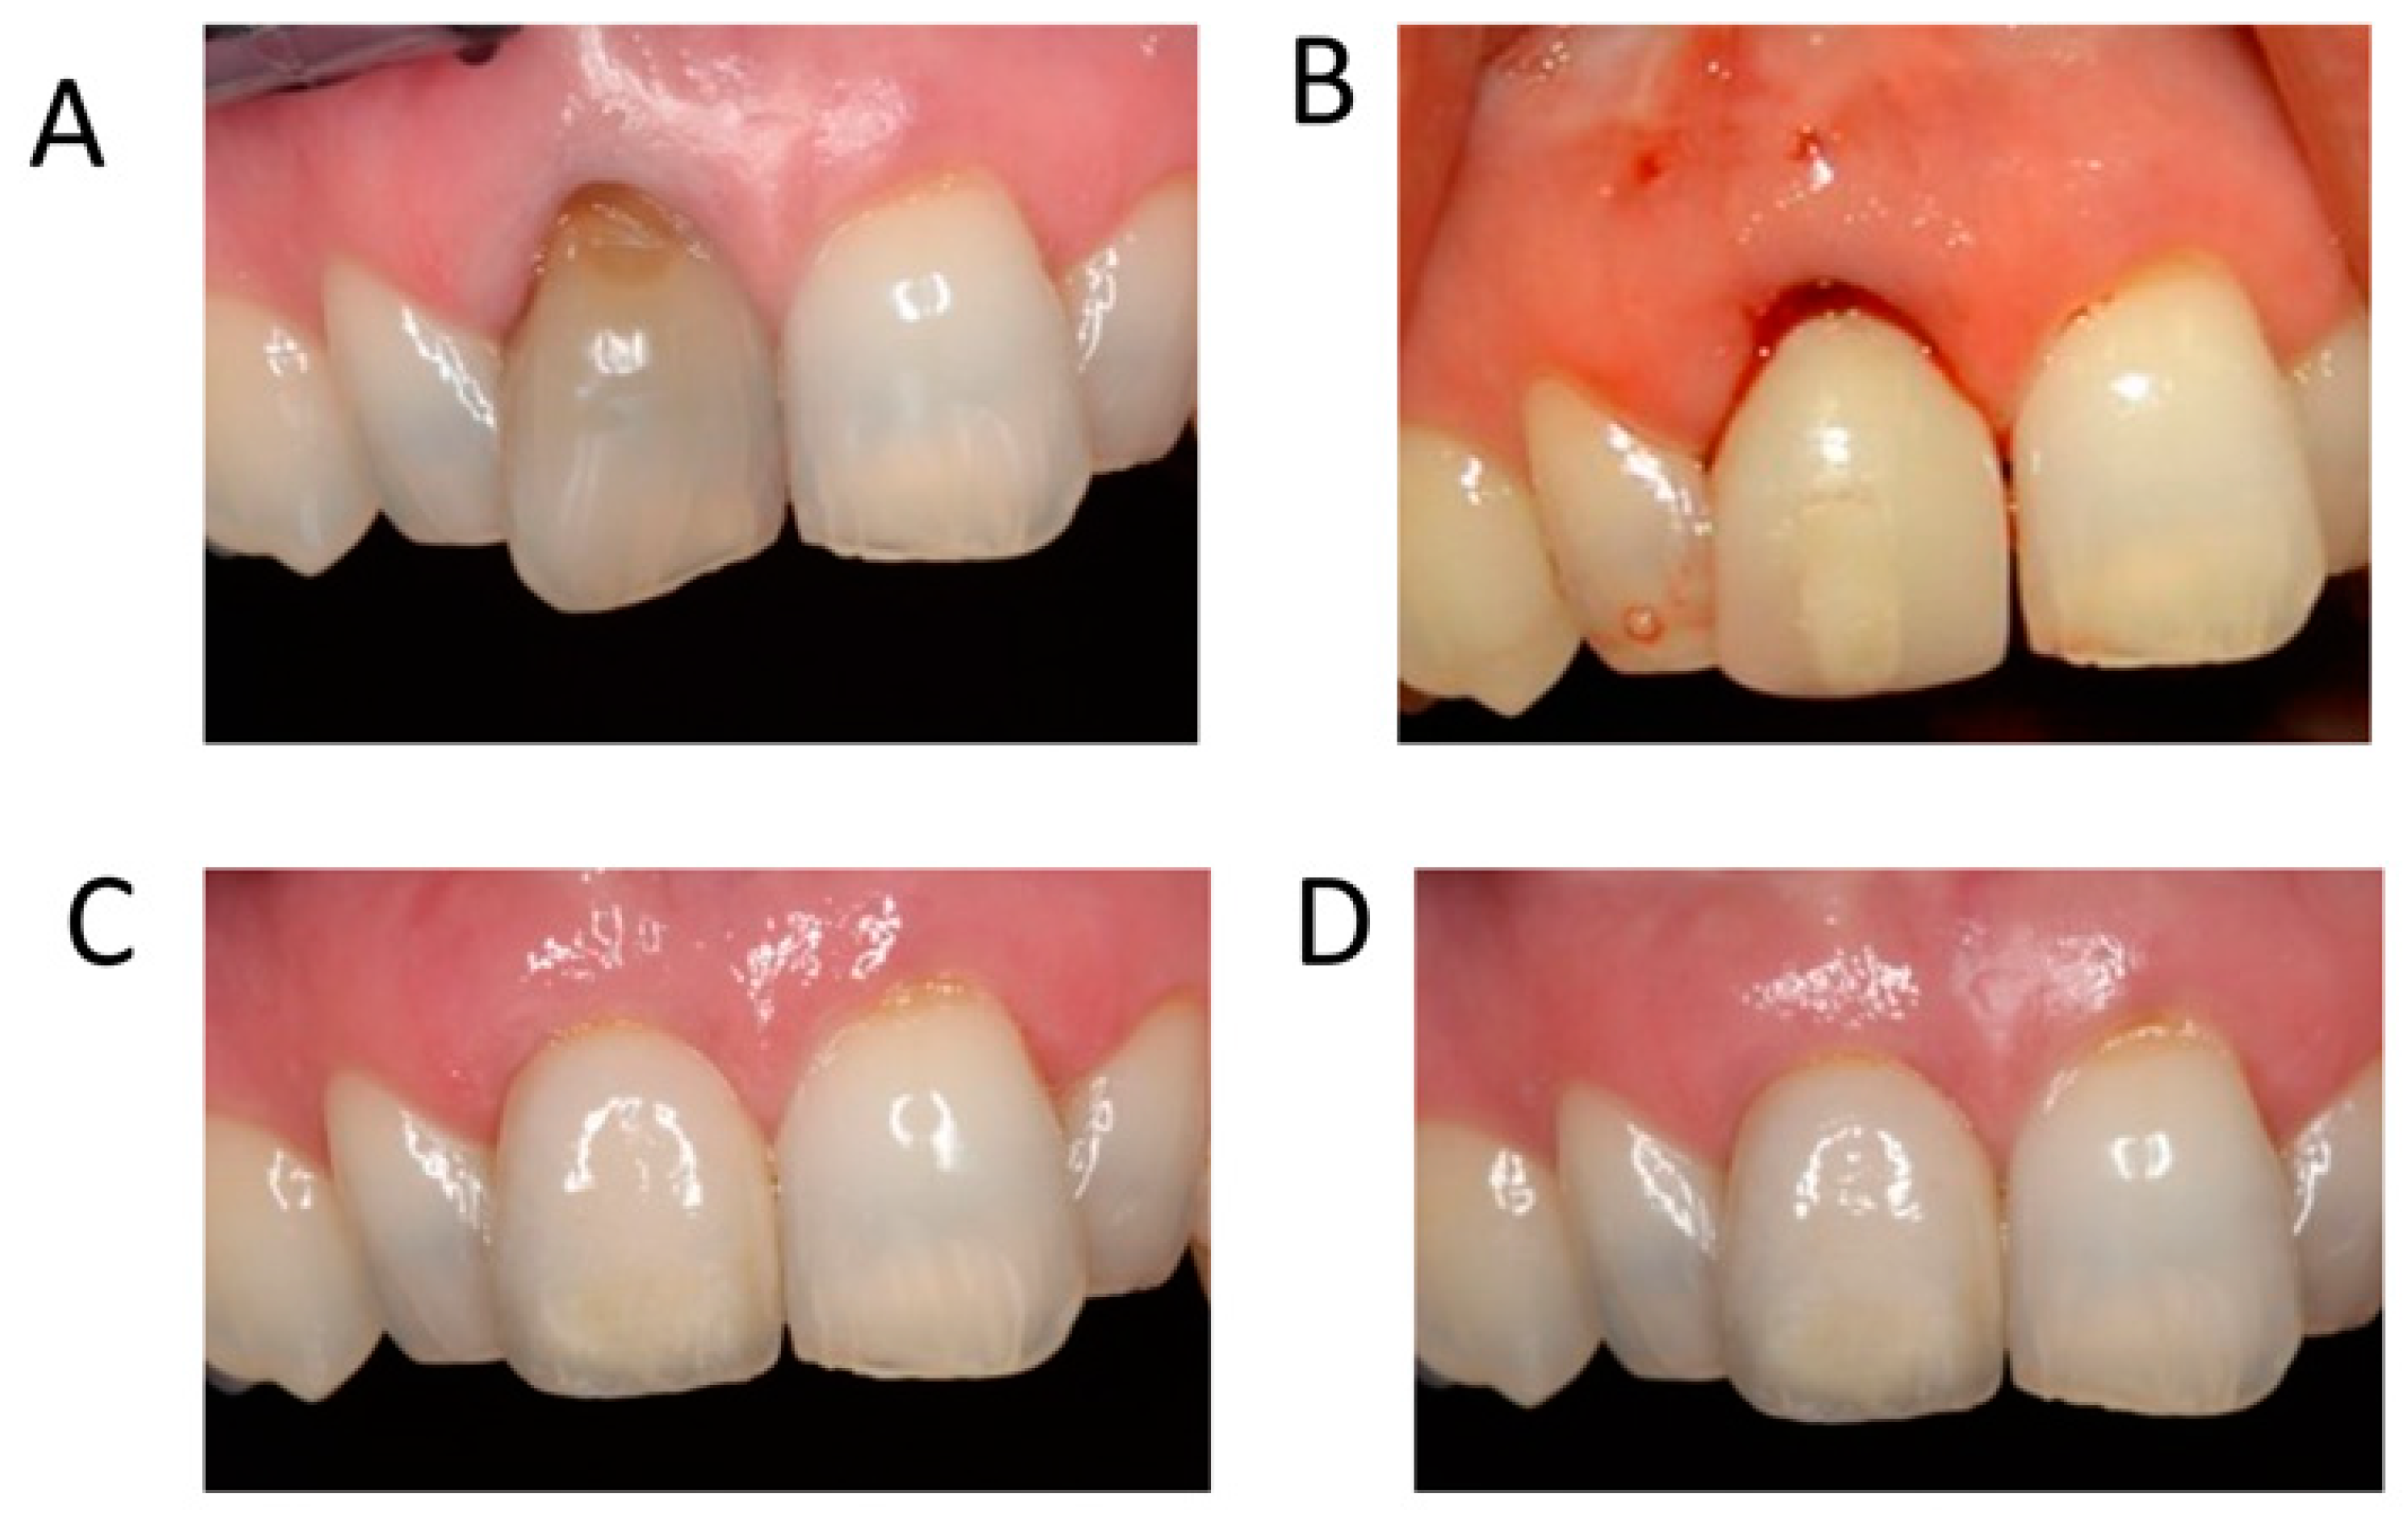

2. Soft versus Hard Tissue Augmentation in the Anterior Region